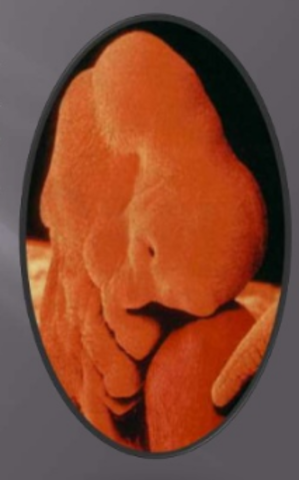

• Quinta semana

Quinta semana

El cerebro aún no regula las pulsaciones por minuto que van desde 140 -150. Se forma la traquea